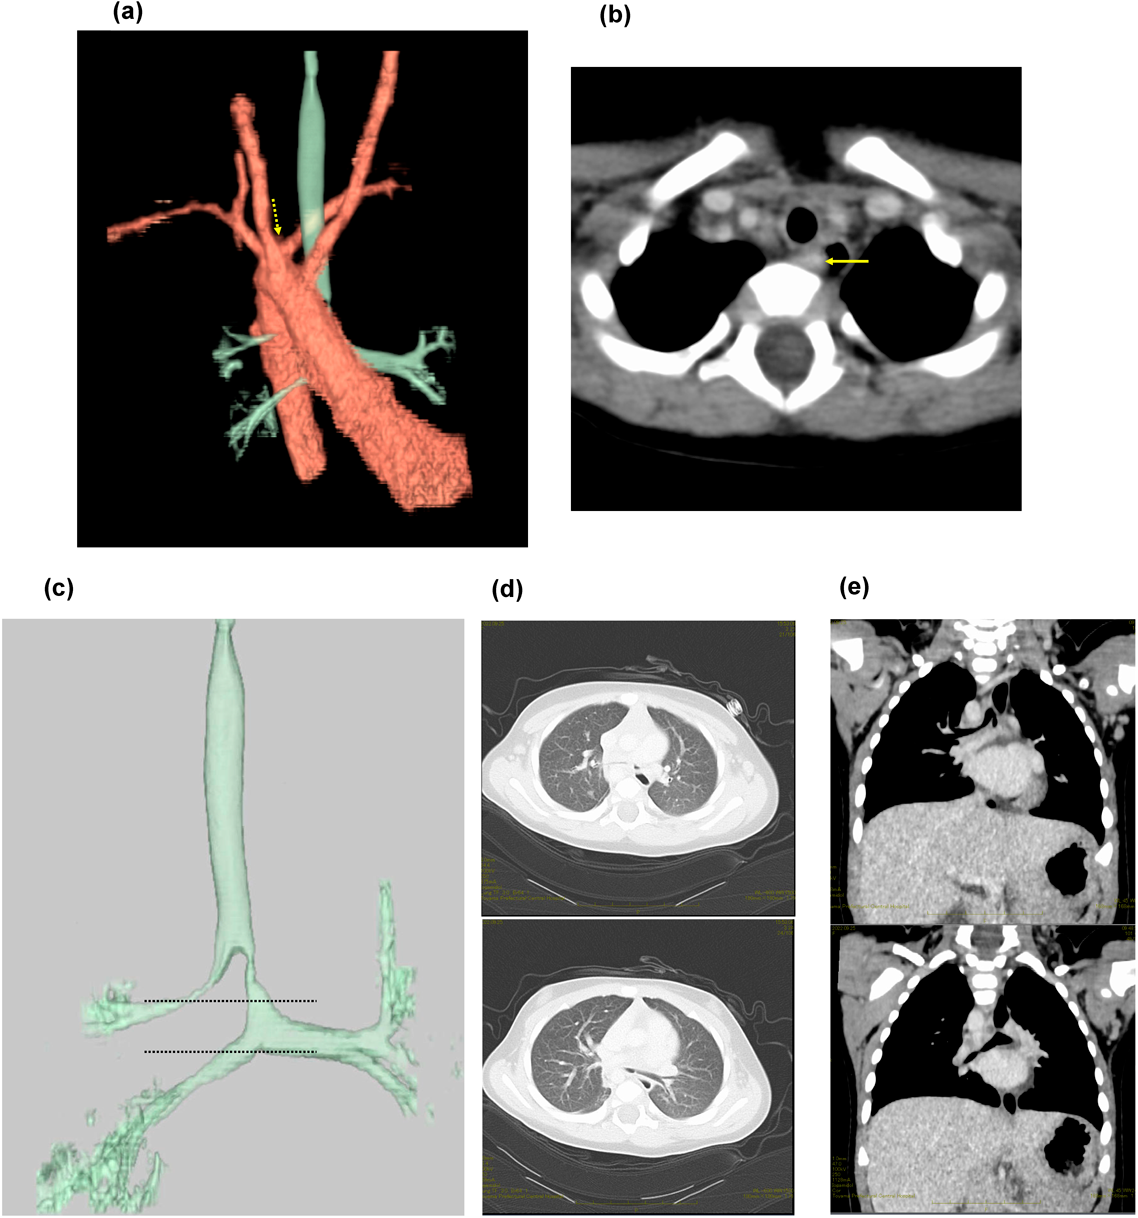

Fig. 2 (a)–(d) Echocardiography of the depicts situs solitus, D-loop, and D-spiral. (e) There was a left-to-right shunt due to a 1.2-mm atrial septal defect

Fig. 3 Contrast-enhanced computed tomography chest scan with three-dimensional reconstruction

(a) Thoracic Contrast CT with 3D reconstruction depicting the aorta, trachea, and bronchus: arrow shows the anomalous origin of the left subclavian artery. (b) Thoracic Contrast CT, axial plane: The trachea was widely patent, despite the presence of an abnormal left subclavian artery extending dorsally. (c) Thoracic contrast CT with 3D reconstruction depicting the trachea and bronchus: bridging bronchus and bronchial stenosis were observed. The right upper lobe bronchus branched above the tracheal bifurcation, forming the tracheal bronchus. The bridging bronchus was characterized by leftward displacement of the tracheal bifurcation and the right middle and lower lobe bronchus traversing the midline. The dotted lines represent the level corresponding to the coronal CT images shown in (d). (d) Thoracic CT depicting the lung anatomy in the patient: The right lung had 3 lobes, and the left lung had 2; there was no homology. (e) Thoracic CT, coronal plane: right upper lobe bronchus dividing into branches above the tracheal bifurcation, known as the tracheal bronchus.

採血では白血球21,900/µL,CRP 0.32 mg/dLと軽度の炎症反応上昇を認めた(Table 1).単純胸部X線ではCTR 42%,含気の左右差と右下肺野に無気肺を認めたが明らかな肺炎像はなかった.また,胃泡は左側,肝臓は右側に認めた(Fig. 1a).心電図所見は正常洞調律でP,QRS波形は一種類のみであった(Fig. 1b).心エコー検査では心房位はsolitus,心室位D-loop,大血管位D-spiralであった.1.2 mmの心房中隔欠損による左右短絡を認め,右側大動脈弓であったが,房室弁や肺静脈還流に異常は認めなかった(Fig. 2a–f).

入院後,気道感染に伴う気管支喘息の増悪としてステロイドの全身投与,吸入による治療を開始した.しかし喘息としてはステロイド,β刺激薬に対する治療への反応に乏しく入院2日目に中止した.入院3日目に喘鳴の増悪を認め,High-flow nasal cannula(HFNC)を導入した.吸気性喘鳴の鑑別のため耳鼻科でファイバー検査を施行したが喉頭軟化症を含め上気道狭窄病変は認めなかった.入院5日目に再度発熱したため採血を再検したところWBC 24200/µL,CRP 1.4 mg/dLと炎症反応の上昇を認め,ABPC/SBT(134 mg/kg/day)の投与を開始した.鼻腔から喉頭までの気道狭窄病変を認めないにもかかわらず,喘鳴が持続したため下気道評価の目的に造影CTを行うこととした.また,事前に鎖肛治療のために受診していた病院の画像・情報提供を取り寄せたところ無脾症候群の疑いがあることが判明したため,腹部も撮影する方針とした.入院9日目に行った造影CTでは心臓・大血管については右大動脈弓であり,左鎖骨下動脈起始異常を伴っていた.水平断では左鎖骨下動脈は気管の後ろを走行していたが気管の圧排・変形は認めなかった.血管走行の異常は認めたが,気管を圧排する所見がなかったことから,血管輪,vascular slingによる喘鳴は否定的と判断した.肺静脈還流異常も含め複雑心疾患は認めず,心耳形態は正常であった(Fig. 3a–e).肺については,右肺は三葉,左肺は二葉で肺葉に相同性はなかった.気管については,右上葉気管支が気管分岐部よりも上部から分岐しており気管気管支の形態であった.気管気管支に加えて右中葉・下葉に向かう気管支が正中をまたいで左から右に遊走する気管走行をしておりbridging bronchusであった.右上葉気管気管支が分枝するレベルで狭窄を認めており喘鳴の原因と考えられた.腹部所見では胆嚢は描出されたが,脾臓は同定できなかった(Fig. 4a, b).後日再検した血液像でHowell Jolly小体を1%認め,複雑心疾患を伴わない無脾症候群と診断した.喘鳴は徐々に改善し,入院9日目にはHFNCから離脱し,入院11日目に退院となった.以降,かかりつけ病院で抗菌薬の予防内服が開始された.